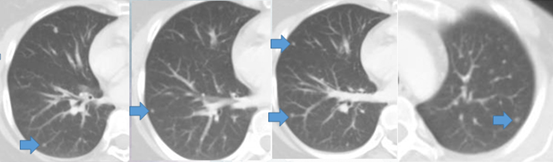

疾病进展:2016-10 CT:双肺散在小结节影,以左肺上叶病灶稍大(0.36×0.34cm)

疾病稳定:2017-10 CT:双肺散在小结节影,以左肺上叶病灶稍大(直径0.5cm)

疾病进展:2018-04 PET-CT:右肺下叶散在直径约0.5cm类圆形结节影,SUVmax约为2.3;左肺上叶尖段直径约0.3cm结节影,显像剂未见摄取增高。右侧肺门淋巴结显示、增大,显像剂摄取增高,SUVmax约为4.9。考虑转移。

疾病稳定:影像学检查:2019-09 肺部CT:双肺多发散在小结节,右肺为甚(最大直径0.5cm)